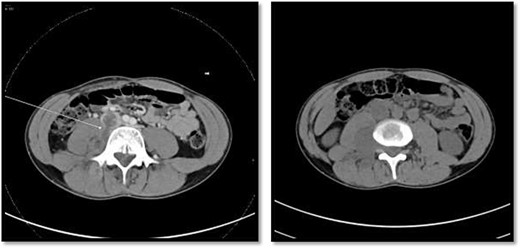

On the left image, there is associated fistulas tract between the mass and infrarenal inferior vena cava with a small hyperdense component may represent hemorrhage or solid component. The right image CT scan showed the mass extending through the neural foramina compressing the spinal cord from the level of the L2–L4.

An 18-year-old healthy man presented to the emergency department (ED) with 1-day history of right testicular pain and vomiting with no fever nor abdominal pain. Physical examination showed mild tenderness in the right testis, no swelling, normal longitudinal position and cremasteric reflex. Scrotal Doppler ultrasound was performed and showed reduced vascularity in the right testis and the left testis was normal. Moreover, the size and echogenicity were maintained for both testes (Fig. 1). Two months prior to this presentation, the patient presented with the same attack with only mild tenderness in the right testis, and all investigations were within normal limits and he was discharged with oral analgesic drugs. The decision was made to undergo surgical exploration for possible torsion/detorsion of the right testis. The patient was transferred immediately to the operating room for bilateral orchiopexy. The right spermatic cord was engorged with no evidence of ischemia identified and bilateral orchiopexy was done successfully. After the surgery, the patient was kept for observation for 24 h and then discharged. After 2 days from the surgery, the patient came back to ED with testicular pain and post-surgical swelling. We decided to do computerized tomography (CT) scan of the abdominal and pelvis to rule out retroperitoneal pathologies or referred pain. The CT showed 4 × 3 cm lobulated mass noted at right paravertebral space invading the right psoas muscle at the level of L3 and L4 (Fig. 2). The CT scan also showed there is an associated fistula tract between the mass and infrarenal inferior vena cava with thrombosis associated with epidural component extending through the neural foramina compressing the spinal cord from the level of the L2–L4 (Fig. 3). The patient was referred to spinal surgery and CT-guided paraspinal lumbar biopsy was taken. The histopathology came with the diagnosis of Ewing sarcoma. The decision was made by the medical oncology to start on a systemic chemotherapy (vincristine + Adriamycin + cyclophosphamide alternating with ifosfamide + etoposide (VAC/IE)) regimen. After six cycles, the follow-up magnetic resonance imaging demonstrated significant resolution of the right psoas and posterior paraspinal metastatic disease. In addition, further resolution with residual intraspinal extradural metastatic disease noted at right L2–3 and L3–4 levels. The patient is still followed up as an outpatient clinic with medical oncology.